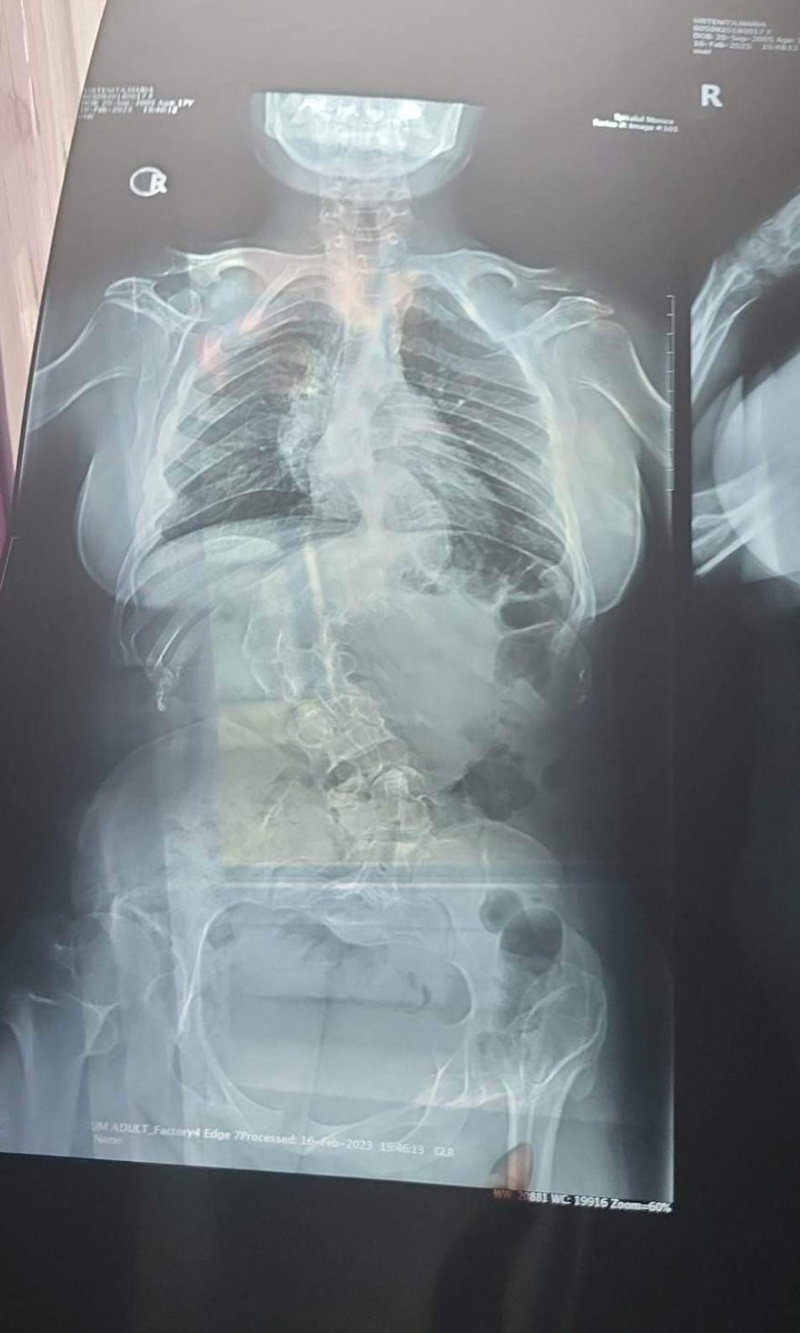

Maria-Bianca Vîrteniță este o tânără în vârstă de 18 ani din comuna Bengești-Ciocadia. Zilele fetei sunt umbrite de o gravă afecțiune de care suferă și care ar putea să îi aducă probleme de sănătate mult mai mari, riscând să îi fie afectați și plămânii. Sora acesteia, Amina Vîrteniță este cea care strigă după ajutor financiar pentru a aduce speranță în ochii Mariei-Bianca și zâmbete pe chip. Oamenii cu suflet mare din județ sunt implorați să doneze din puținul lor pentru ca Maria-Bianca să primească o șansă la o viață normală și să se poată bucura de tinerețe. ,,Sora mea, în vârstă de 18 ani, suferă de scolioză dorso-lombara. Pe viitor pot apărea probleme cu plămânii. Nimeni nu i-a dat șanse până acum, însă acum a primit șansă să se opereze, dar este nevoie de o sumă enormă, mai precis de 30.000 de euro. Zilele trecute, medicii de la Spitalul Monza din București care i-au făcut o nouă investigație au decis că pot interveni și o pot opera în această lună, pe 26 martie. Operația durează între 20 și 26 de ore, fiind nevoiți să-i scoată două vertebre. Oricine are bunăvoință să ne ajute, din puținul vostru, puneți dona aici: Nume titular: Virtenita Maria-Bianca, Cont: RO28 BRDE 200S V760 9080 2000, Moneda: RON”, este apelul făcut de Amina Vîrteniță pentru salvarea surorii sale.